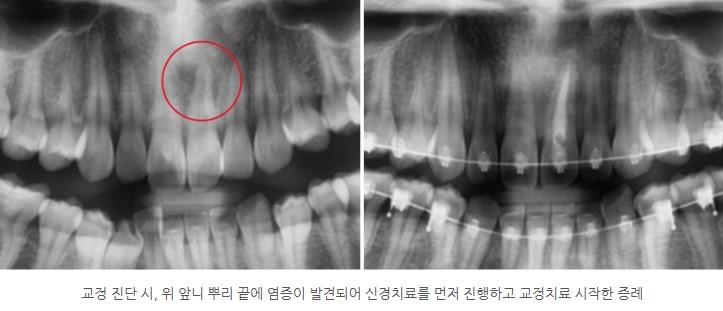

아래 증례는

교정 진단 시 위 앞니 뿌리 끝 염증이 발견되어

신경치료를 먼저 완료한 후 교정을 시작한 경우입니다.